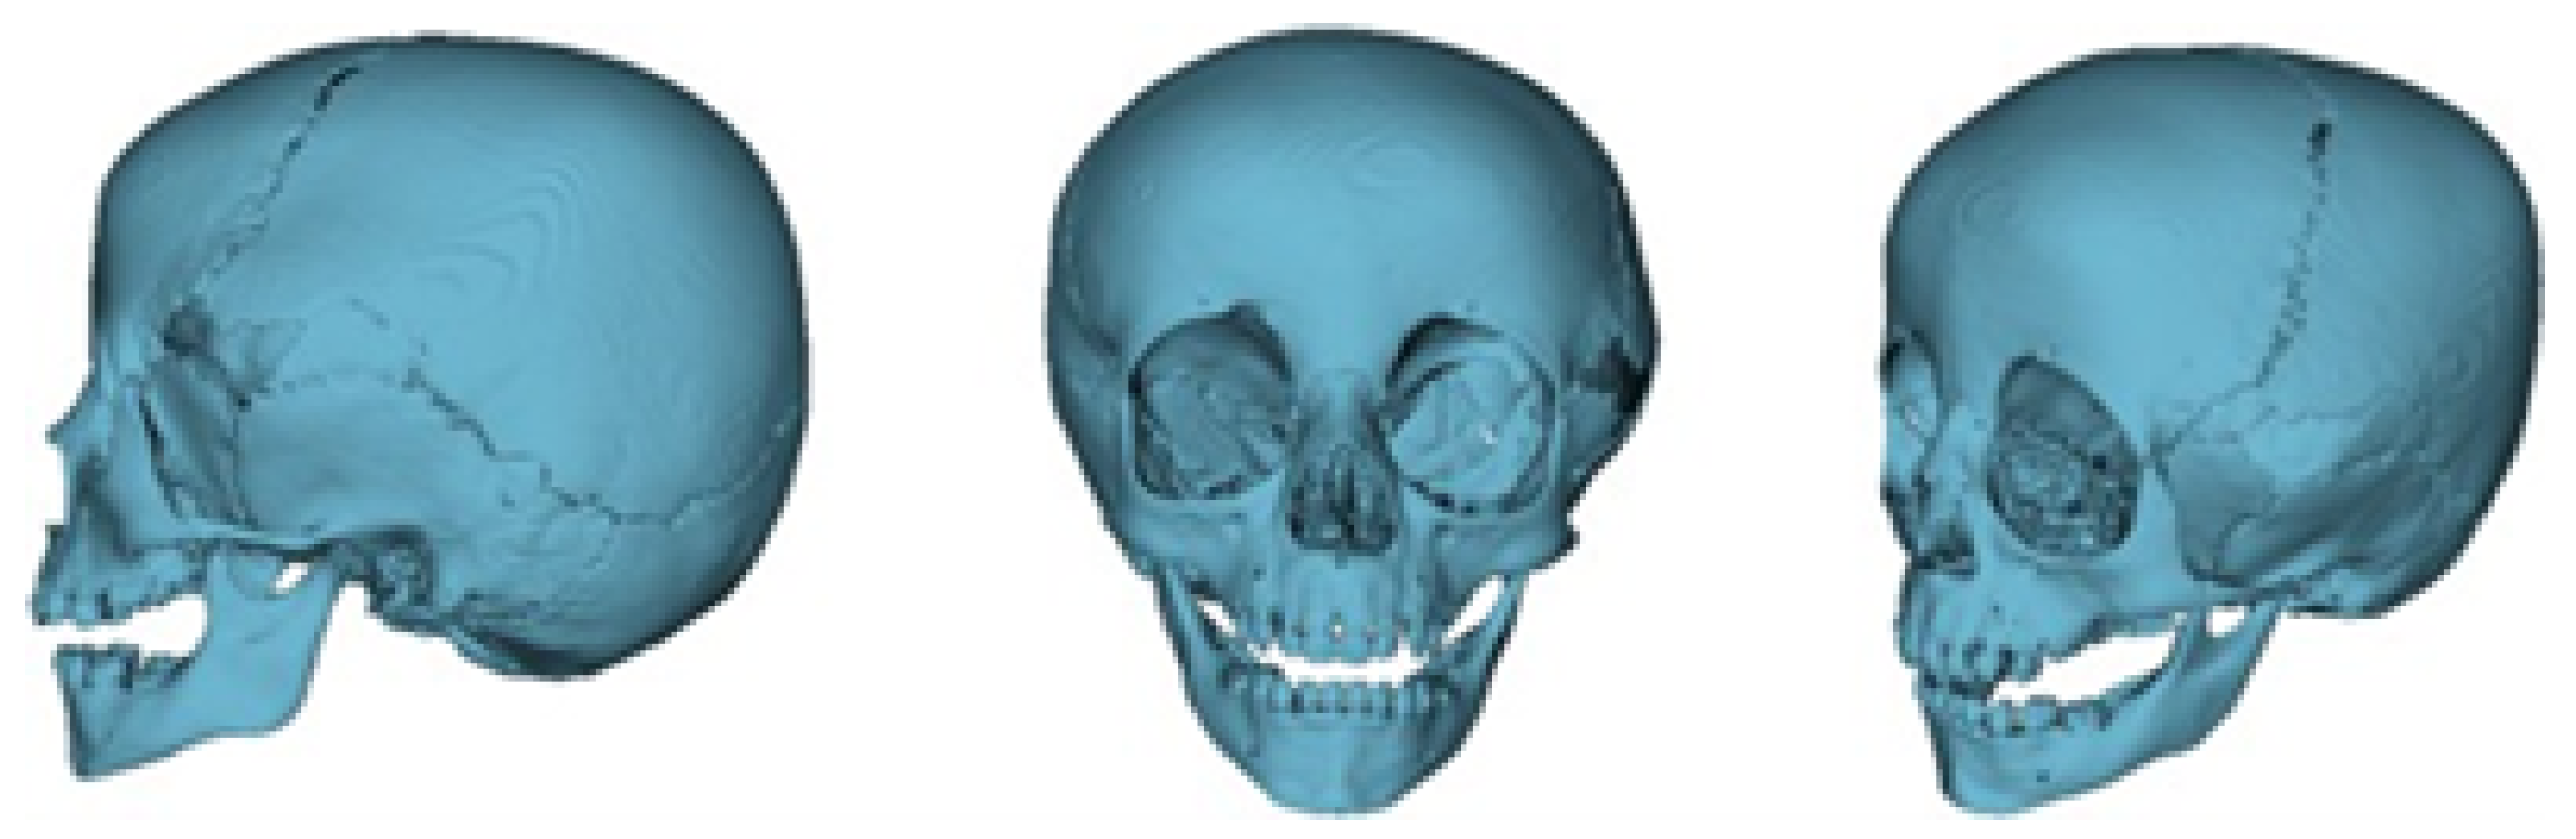

The defects identified were corroborated by both the patient’s medical history and physical examinations, as well as by tomography. The tomographic images were then segmented to reconstruct the left temporo-parietal cranial bone tissue. The density of compact cranial tissue was established using a range of 180 to 2000 HU (see Figure 3 and Figure 4).

The segmentation process facilitated the correlation of the digital anatomical model (in which the left temporoparietal defect was identified) and the physical anatomical model for simulated surgical planning (see Figure 5 and Figure 6).

Figure 6. Three-dimensional anatomical model of the skull and cutting plan.